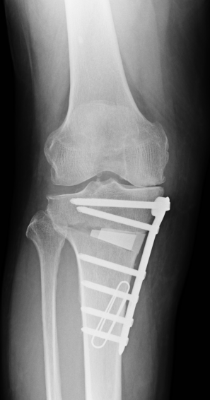

変形性膝関節症の術前

高位脛骨骨切り術

骨切り術の術後

人工膝関節全置換術(左:手術前、右:手術後)